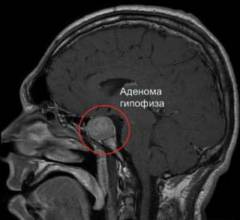

Аденома гипофиза – доброкачественная опухоль, характеризующаяся разрастанием клеток передней доли железы.

Аденома гипофиза — доброкачественная опухоль, возникающая из клеток передней доли железы.

Избыточная выработка соматотропина может привести к акромегалии, проявляющейся ростом и увеличением размеров тела, чаще всего в возрасте 30–50 лет. У детей это состояние вызывает гигантизм.

В зависимости от размеров аденомы выделяют:

- пикоаденому (до 3 мм);

- микроаденому (до 10 мм);

- макроаденому (более 10 мм);

- гигантские аденомы (от 40 до 50 мм и более).

Около 99% случаев акромегалии связано с аденомой гипофиза — доброкачественной опухолью, возникающей из-за чрезмерного деления клеток передней доли гипофиза. Это приводит к увеличению уровня соматотропина и, со временем, к акромегалии.

Размеры опухоли могут варьироваться от нескольких миллиметров до сантиметров. На поздних стадиях опухоль может сжимать окружающие области мозга, включая сосуды и нервы, что вызывает симптомы, такие как ухудшение зрения, головные боли и повышение внутричерепного давления.